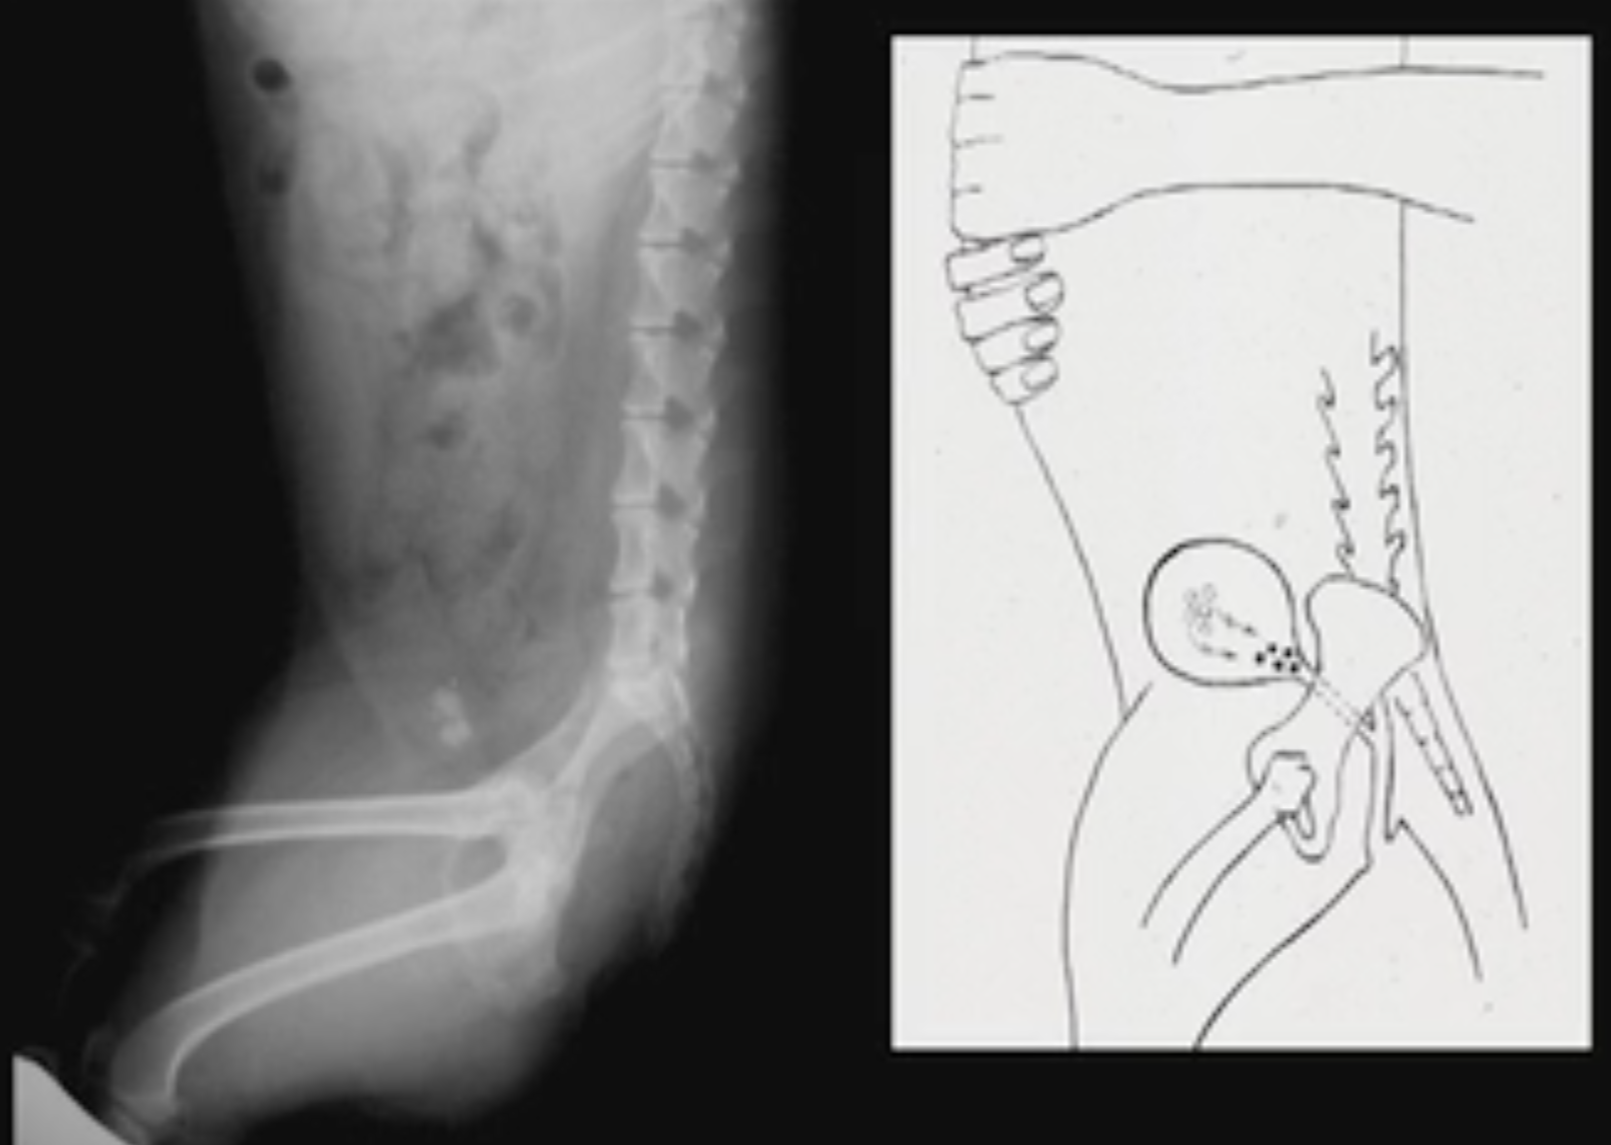

Cystotomy is over 150 years old and much has not changed. Surgeons still leave stones behind and suture material in the bladder lumen causes 10 to 20% of recurrences. This presentation tells the story behind voiding urohydropropulsion and uses a case to discuss how the procedure is used. We will also discuss the three most important strategies to prevent calcium oxalate urolith recurrence.